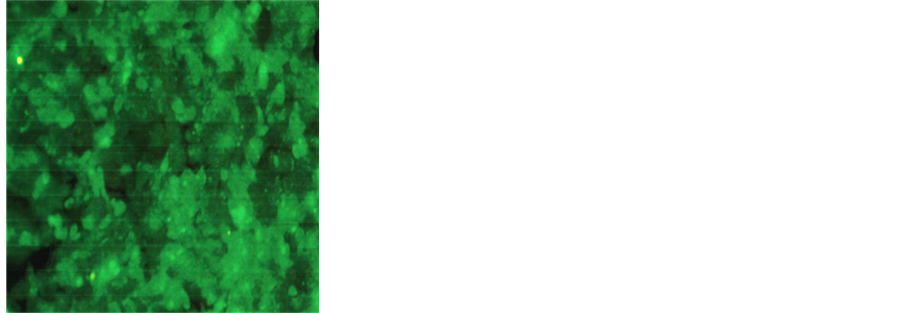

3.3. Nutrient Mixture Induced Morphological Changes Associated with Apoptosis

The DU-145 cells were stained by using H & E to detect apoptotic cells which show the characteristic morphological changes such as the shrinkage of the cytoplasm and darkly stained nuclei with intensely acidophilic cytoplasm. H & E staining of DU-145 cells treated with the nutrient formulation showed that with increasing concentrations of NM the cells showed extensive cell shrinkage, rounding and nuclear condensation (Figure 4). The changes were dose dependent, increasing in intensity with increasing NM concentrations.

Figure 4. Effect of NM on morphological changes: H & E staining of prostate cancer DU-145 cells treated with (a) 0 mg/ml, (b) 100 mg/ml, (c) 500 mg/ml, (d) 1000 mg/ml concentrations of NM respectively.

Morphological changes characteristic of apoptotic cells such as cell shrinkage, nuclear compaction, loss of membrane symmetry and condensation of the cytoplasm were also analyzed. Upon treatment of DU-145 prostate cancer cells with 100, 500 and 1000 μg/ml of NM, it was found that the progressive rounding of cells and nuclear condensation showed a dose dependent increase.